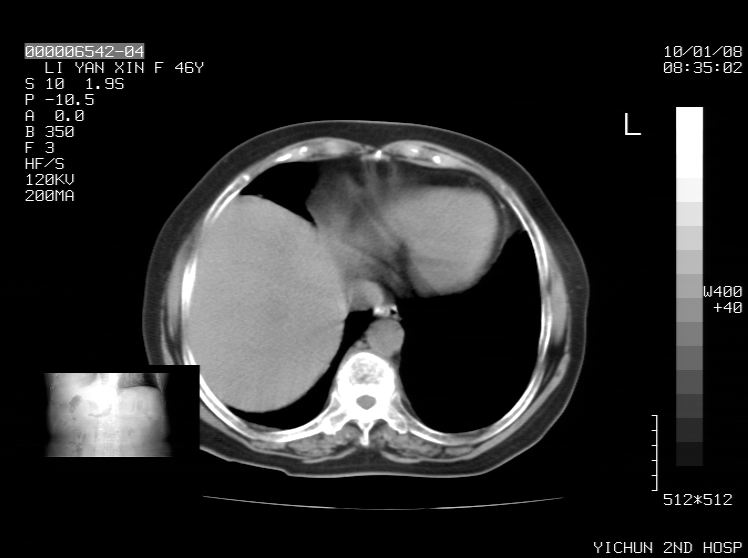

右侧膈膨升,胆囊壁厚,右侧肾脏缺如。病史?

右侧膈膨升,右肾脏切除术后

右侧膈膨升,肝内钙化灶,胆囊壁厚,右侧肾脏缺如。病史?

右膈膨出,肝脏变异,肝内钙化,右肾缺如,脾大。

右侧膈膨升,肝内胆管结石?

右侧肾脏缺如。病史?

右侧膈膨升,胆囊壁厚,右侧肾脏缺如,增强,腔静脉旁是否是移位肾

肝脏变异致膈升高,肝左叶肝内胆管结石.右肾萎缩,左肾代偿肥大.

胆囊ct未见确切异常,请结合b超。右侧肾窝未见确切肾脏影,右肾萎缩?异位?

右侧膈膨升,肝内钙化灶,胆囊壁厚,右肾萎缩或发育不良。